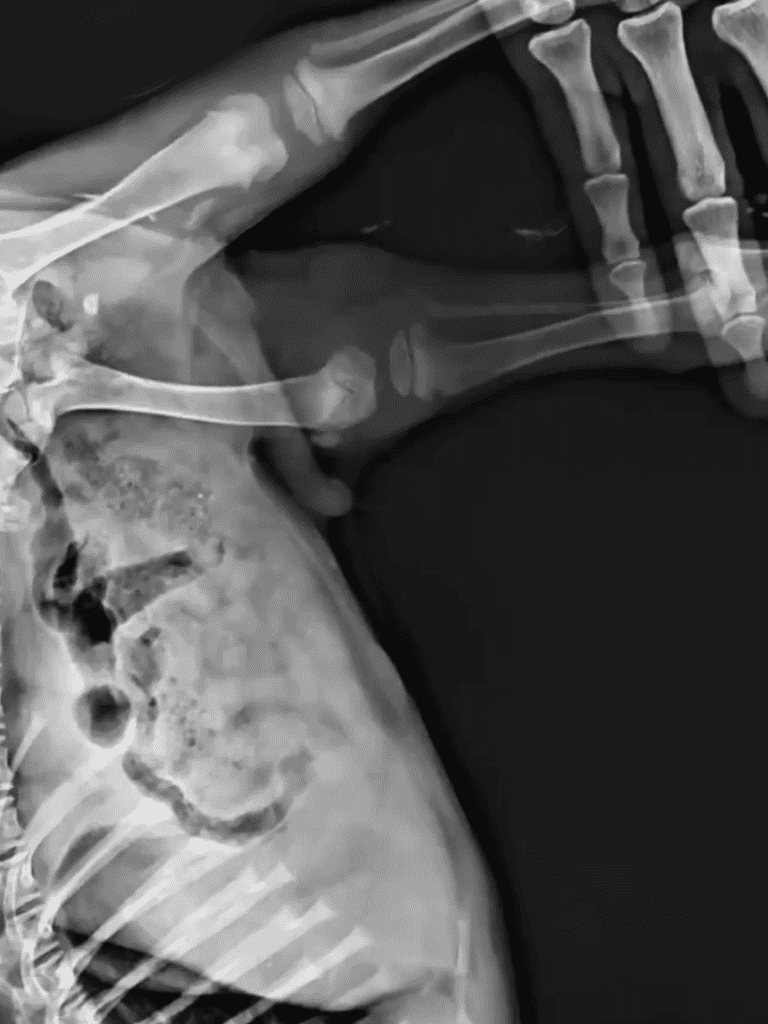

At the veterinary hospital, the X-ray machine hummed as the puppy lay still, its body showing quiet resilience. Despite exhaustion, it cooperated patiently. Lisa stood nearby, her heart aching for the pup.

The vet reviewed the X-rays, revealing an untreated comminuted fracture. Surgery was possible but costly and complex, requiring additional procedures as the puppy grew.

The vet explained the surgery would be challenging and costly due to improperly healed fractures. He mentioned a metal plate might require adjustment later and suggested a wheelchair temporarily.